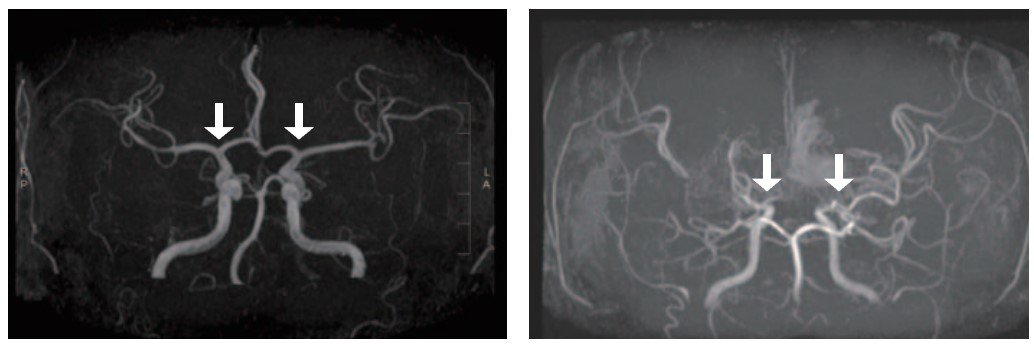

모야모야병은 특별한 원인 없이 대뇌에 혈액을 공급하는 내경동맥의 혈관이 서서히 좁아지는 만성 진행성 뇌혈관질환이다. 이로 인해 혈류가 부족해 지고, 부족한 혈류를 보충하려는 비정상적인 미세혈관이 자라나지만, 이 혈관들은 충분한 혈액을 공급하지 못하고 터지기 쉬워 뇌경색 뇌출혈과 같은 심각한 소아 뇌졸중을 유발하게 된다.

기존에는 모야모야병을 확진하기 위해서는 침습적인 뇌혈관 조영술이 표준 검사였고, 이는 소아에게 큰 부담을 줬다. MRI(자기공명영상)·MRA(자기공명혈관조영술)과 같은 비침습적 검사도 있지만, 모야모야혈관을 자세하게 평가하기 어려워 조기 진단에는 한계가 있었다.